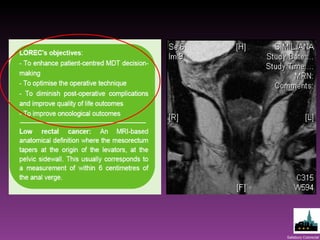

Where did LOREC come from?  Variation in APE rates High CRM involvement Poor outcomes in APE

Proportion APE -28 LOREC MDTs  Mean 24% (14 -44%) National Cancer Intelligence Network (Andy McMeeking)